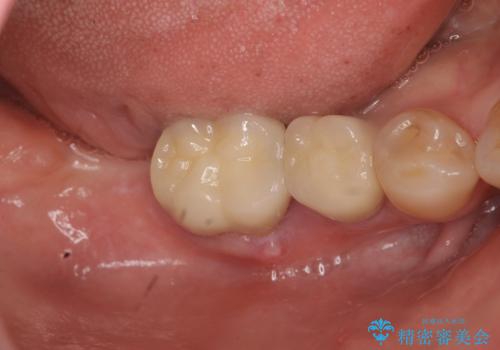

奥歯から膿のにおいがする インプラントによる機能回復

- 99万円(インプラント×2・チタンカスタムアバットメント×2・ジルコニアクラウン×2・仮歯×2)費用は治療当時の料金となります

破折した歯はほとんどの場合抜歯が必要になることが多く、インプラントを用いた咬合機能の回復は、また噛めるようになるだけでなく残っているその他の歯を守る意味でも非常に大きな意味を持ちます。